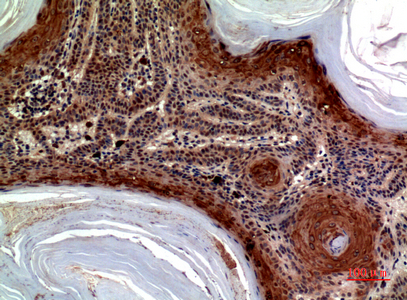

Facts about C-C motif chemokine 27.

Binds to CCR10. .

ALP; C-C motif chemokine 27; CCL27; chemokine (C-C motif) ligand 27; CTACK; CTACKSmall-inducible cytokine A27; CTAK; cutaneous T-cell attracting chemokine; Cutaneous T-cell-attracting chemokine; ESKINE; IL-11 Ralpha-locus chemokine; ILC; ILCCC chemokine ILC; PESKY; SCYA27IL-11 R-alpha-locus chemokine; skinkine; small inducible cytokine subfamily A (Cys-Cys), member 27

Testis, thymus, placenta, ovary and skin.